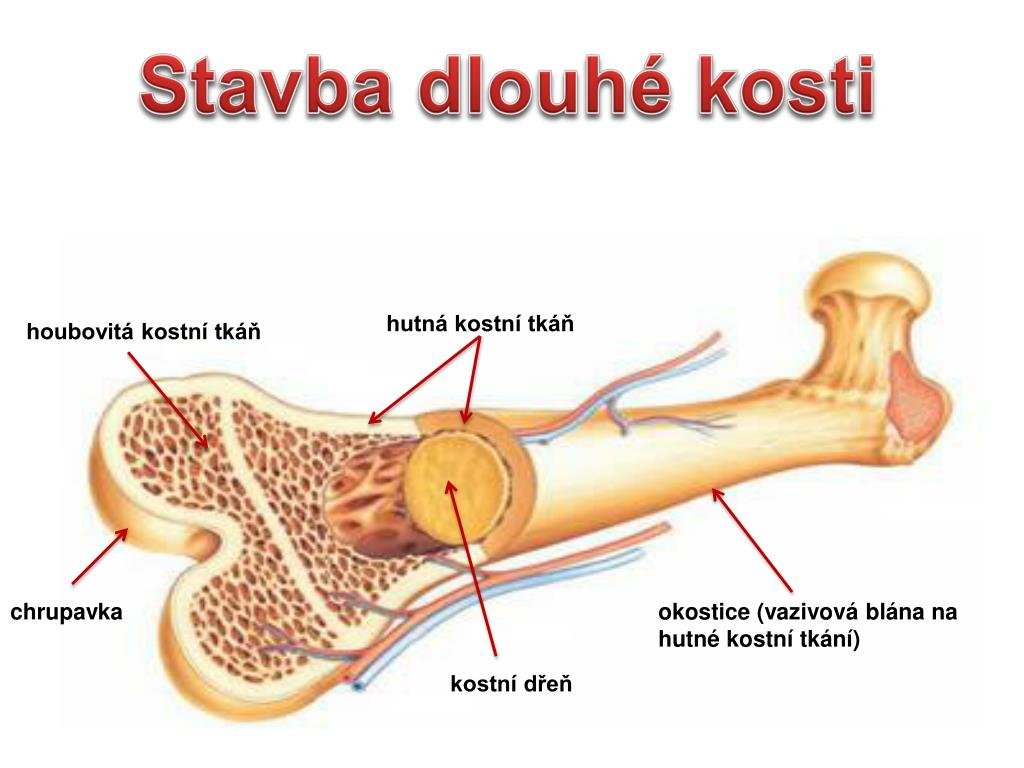

Изучение костного мозга: анатомия и функции